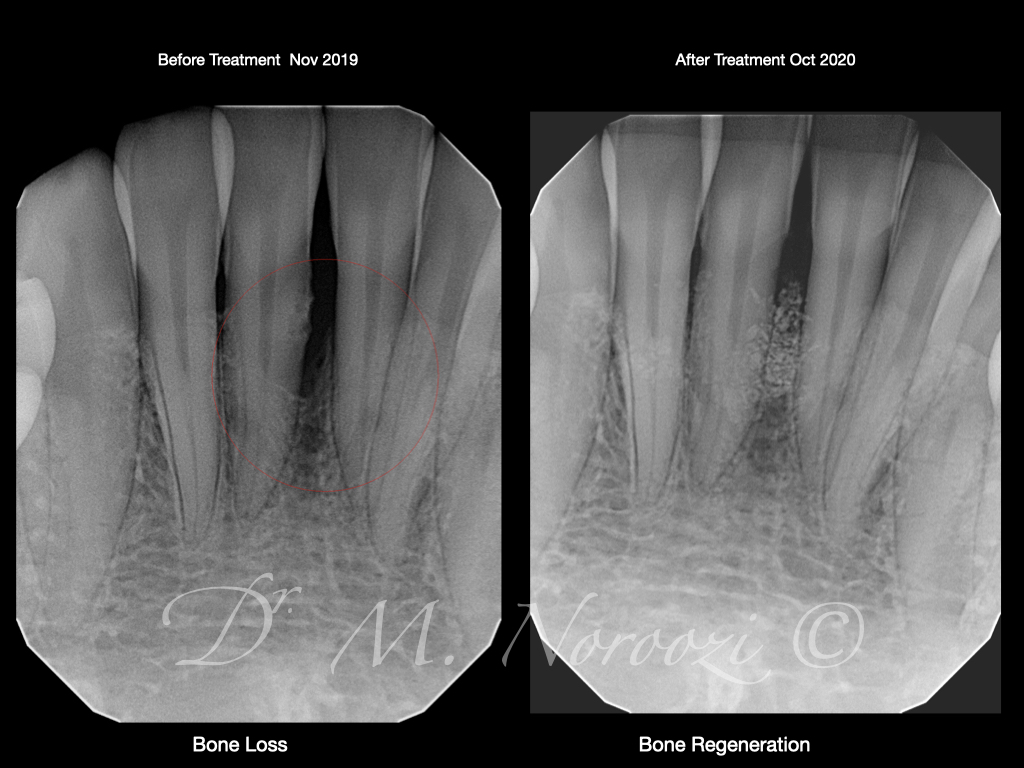

Guided Tissue Regeneration with Bone Graft & Growth Factors to Save teeth